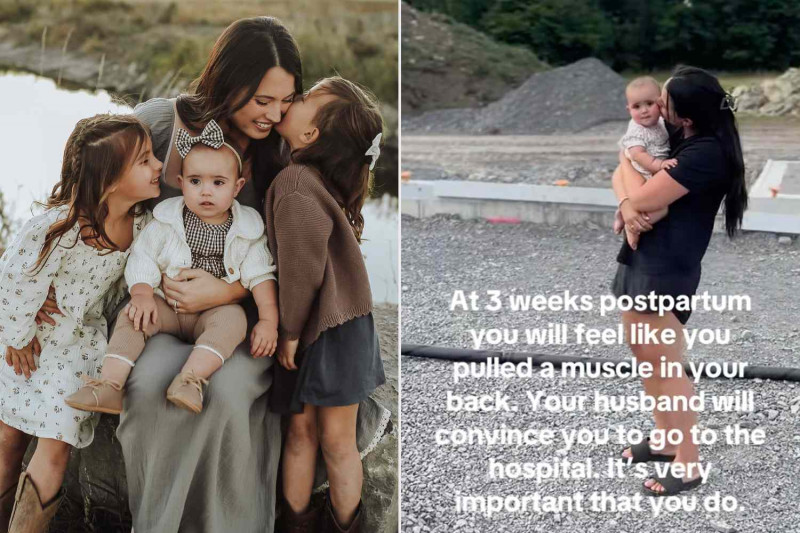

News source#BreastCancer #CancerAwareness #PrenatalCare

#MaternalHealth #PulmonaryEmbolism #HealthAwareness